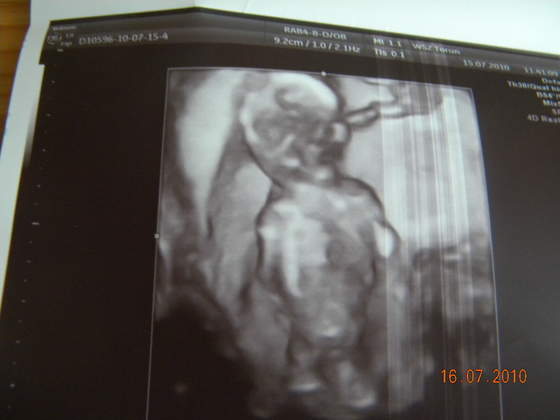

byliśmy z brzuszkiem wczoraj na wizycie kontrolnej i udało nam się namówić ginka na usg ;-)nawet nie specjalnie dał się prosić

ginek mówił że tylko takie szybkie usg zrobimy, a wyszło dłużej niż usg przezierności karkowej

Kajetanek (?) rośnie jak na drożdżach i ma już 9,30 cm, ginek chciał zajżeć pomiędzy nóżki ale wstydzioszek je podkurczyłi na koniec odwrócił się do nas dupką

Zobacz załącznik 265045Zobacz załącznik 265046